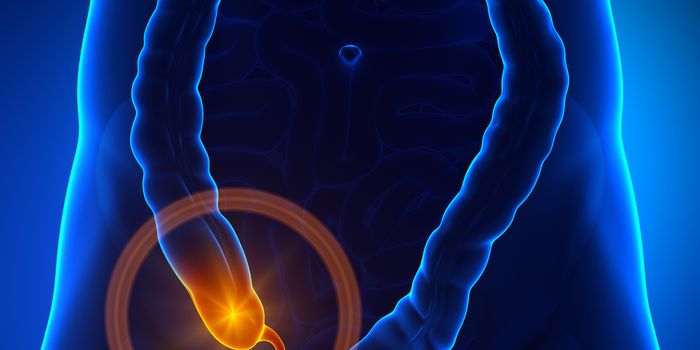

JAN 10, 2017ImmunologyThe body organ known as the appendix has long been claimed to have no known function, but recent research has shown that ...